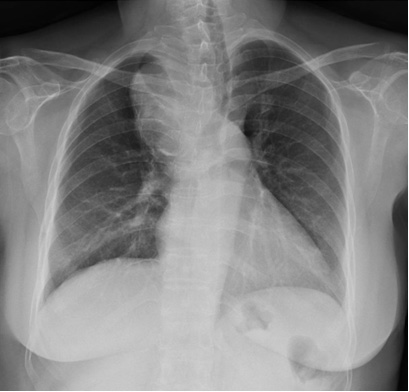

19 / M, Chief complaint: Recurrent episode of chest pain and cardiac enzyme elevation with normal coronary angiography, family history of sudden cardiac arrest

Jinwoo Son, Severance Hospital, Yonsei University College of Medicine